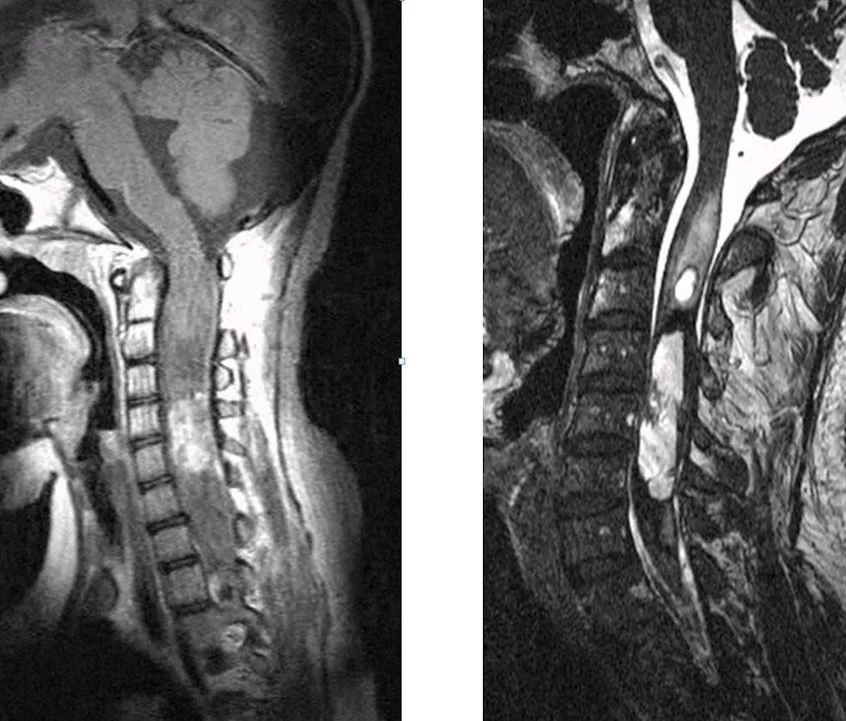

Οι ενδομυελικοί όγκοι αναπτύσσονται εντός του νωτιαίου μυελού (Εικόνα 1). Η συχνότητά τους σε σχέση με τους υπόλοιπους όγκους νωτιαίου μυελού είναι 5%. Τα αστροκυττώματα (στα παιδιά κυρίως) και τα επενδυμώματα (στους ενήλικες κυρίως) είναι οι συχνότεροι τύποι. Λιγότερο συχνοί τύποι είναι τα αιμαγγειοβλαστώματα, σηραγγώδη αγγειώματα και τα λιπώματα.

Παράδειγμα εξωσκληρίδιου όγκου: Ασθενής Άρρεν, 73 ετών, με γνωστή μεταστατική μάζα στον Θ10 σπόνδυλο, η οποίοα προκαλεί σημαντική στένωση του σπονδυλικού σωλήνα και πίεση επί του νωτιαίου μυελού. Διενεργήθη αποσυμπίεση του νωτιαίου μυελού και διαδερμική σπονδυλοδεσία/σπονδυλοπλαστική Θ9-Θ10. Μετεγχειρητικά ο ασθενής ανέφερε σημαντική πίεση του άλγους του και σημαντική βελτίωση της βάδισης.

Μαγνητική Τομογραφία: Η μαγνητική τομογραφία με σκιαγραφικό είναι η εξέταση εκλογής για τους όγκους σπονδυλικής στήλης. Θα δείξει με ακρίβεια την θέση και έκταση της βλάβης και θα δώσει και πολύτιμες πληροφορίες ώς προς τη φύση του όγκου (πχ. ένα μηνιγγίωμα θωρακικής μοίρας θα φανεί εξαιρετικά σε μια μαγνητική τομογραφία θωρακικής μοίρας και νωτιαίου μυελού).

Χειρουργική Αντιμετώπιση: Οι ενδείξεις και ο τρόπος χειρουργικής αντιμετώπισης εξαρτώνται απολύτως από τον τύπο του όγκου. Πρωτοπαθείς (μη-μεταστατικοί) όγκοι των σπονδύλων χρειάζονται ριζική αφαίρεση με σπονδυλεκτομές. Σε περίπτωση μεταστάσεων συνήθως αρκεί η αποσυμπίεση των νευρικών δομών και η συμπληρωματική ακτινοβολία. Το αν υπάρχει ένδειξη για χειρουργείο σε ασθενή με μεταστατική νόσο σπονδυλικής στήλης είναι κάτι που πρέπει να συζητηθεί και να συναποφασιστεί με τους ογκολόγους. Για ενδοσκληρίδους όγκους όπως πχ. μηνιγγιώματα ή νευρινώματα, καθώς επίσης για ενδομυελικούς όγκους (πχ. αστροκυττώματα ή επενδυμώματα) η θεραπεία είναι η ολική χειρουργική αφαίρεση. Συνήθως χρησιμοποιούνται ελάχιστα επεμβατικές μέθοδοι ενώ αποφεύγεται η καταστροφή των υγιών ιστών και δομών της σπονδυλικής στήλης (Εικόνα 3). Μερικοί όγκοι, όπως πχ. το λίπωμα νωτιαίου μυελού, αφαιρούνται ιδιαίτερα αποτελεσματικά με τη χρήση λέιζερ (laser) (Εικόνα 4).